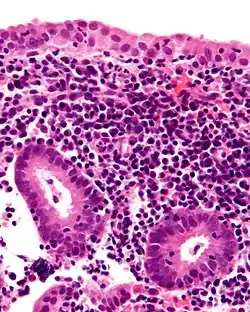

Micrograph showing a chronic endometritis with the characteristic plasma cells. Scattered neutrophils are also present. H&E stain.

Chronic endometritis is characterized by the presence of plasma cells in the stroma. Lymphocytes, eosinophils, and even lymphoid follicles may be seen, but in the absence of plasma cells, are not enough to warrant a histologic diagnosis. It may be seen in up to 10% of all endometrial biopsies performed for irregular bleeding. The most common organisms are Chlamydia trachomatis (chlamydia), Neisseria gonorrhoeae (gonorrhea), Streptococcus agalactiae (Group B Streptococcus), Mycoplasma hominis, tuberculosis, and various viruses. Most of these agents are capable of causing chronic pelvic inflammatory disease (PID). Patients with chronic endometritis may have an underlying cancer of the cervix or endometrium (although an infectious cause is more common). Antibiotic therapy is curative in most cases (depending on the underlying cause), with fairly rapid alleviation of symptoms after only 2 to 3 days. Women with chronic endometritis are also at a higher risk of pregnancy loss, and treatment for this improves future pregnancy outcomes.[17][18]